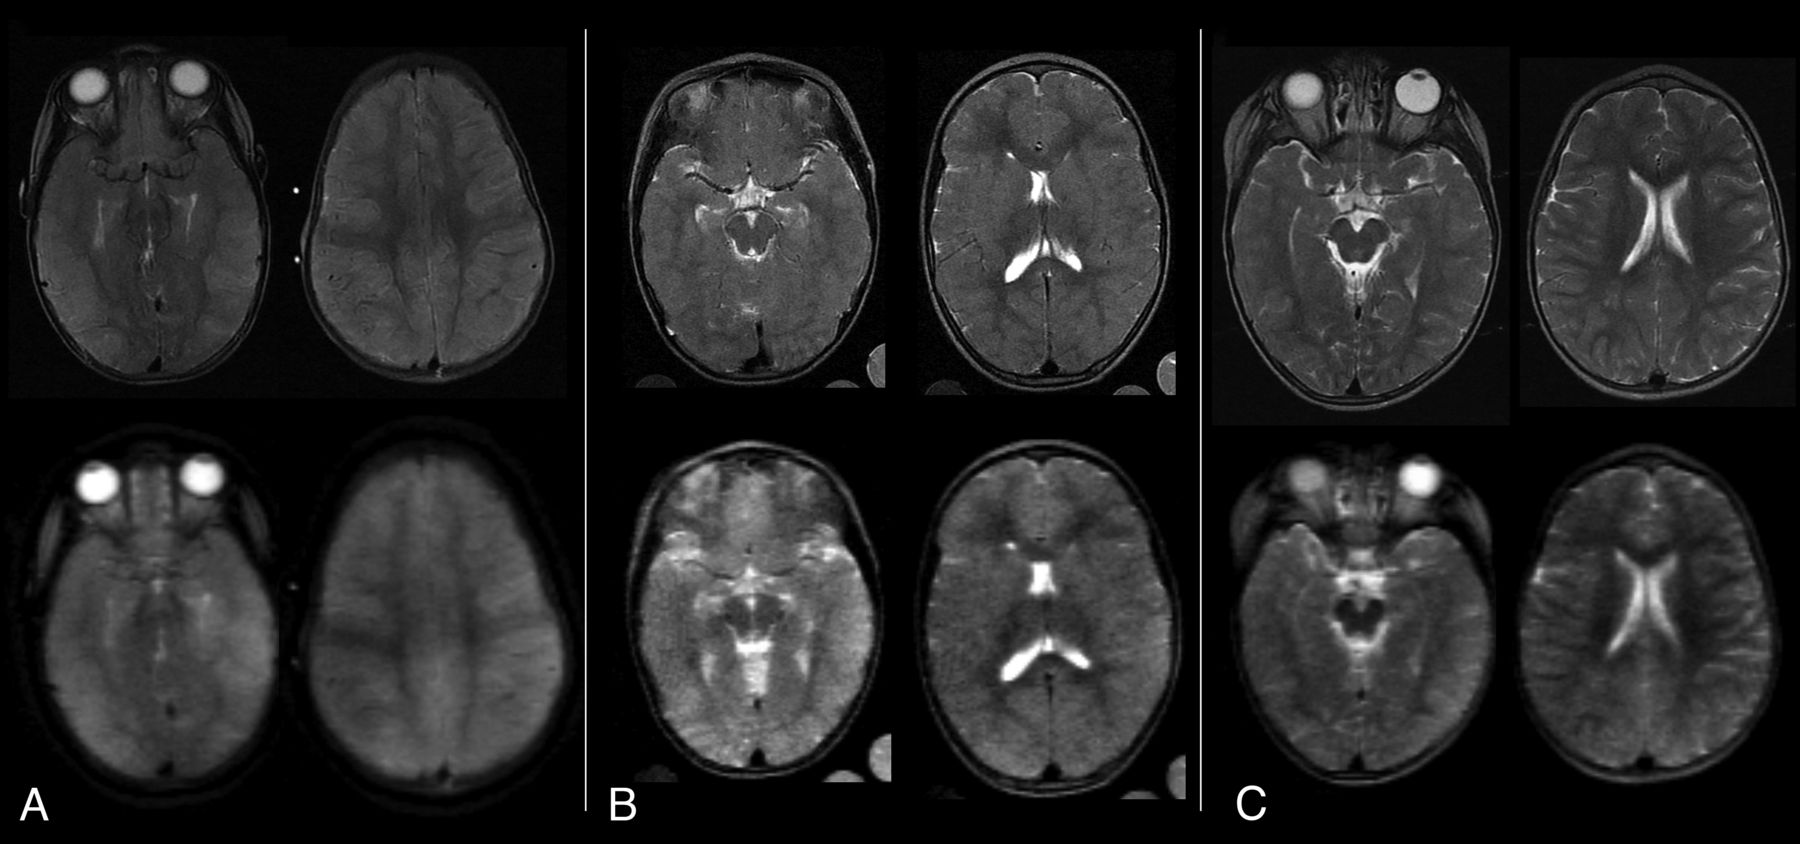

Despite the images being of lower resolution, MRIs degraded to simulate the output of lower-field scanners showed similar characteristics compared with the original images obtained at 0.35 T (Fig 2). The CSF spaces, including the sulci, cisterns, and ventricles, could be differentiated from brain parenchyma, allowing assessment of whether they were effaced. In contrast, blurring of the gray-white junction was less visible using the degraded images compared with those that were not degraded.

Sample T2w original and simulated MRIs from children with CM. The original brain MRIs were obtained on a Signa Ovation 0.35 T magnet (upper row) and corresponding axial images were obtained after image degradation to simulate the resolution of a very-low-field scanner (lower row). A, A BVS of 8 was assigned to the original scan as well as to the degraded images by all 3 radiologists. B, A BVS of 6 was assigned to the original scan, and 6 or 7, to the degraded images. C, A BVS of 4 was assigned to the original scan, and 5 or 3, to the degraded images.